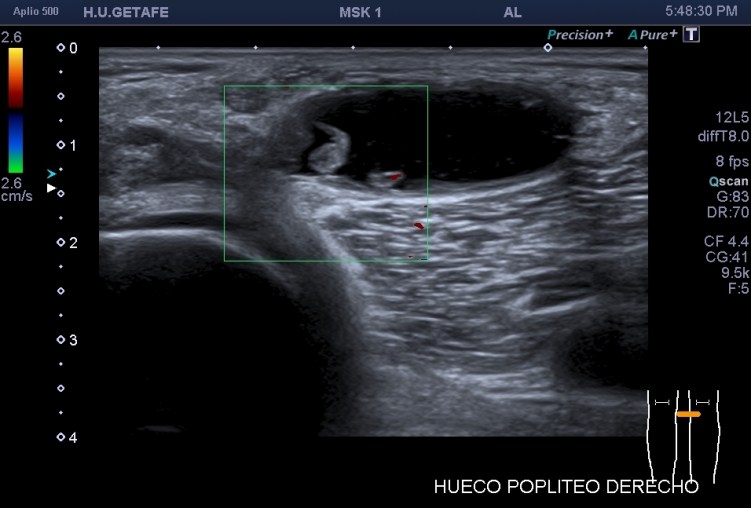

Recuerdo la importancia de comprobar siempre la permeabilidad de los vasos del hueco poplíteo con este tipo de patologías, el parecido de los síntomas de un quiste de Baker roto y la TVP puede ser muy similar y sin embargo, la TVP es una patología potencialmente peligrosa. Para ello pide al paciente que suba la pierna afectada por encima de su otra pierna para poder hacer que el retorno venoso sea más evidente y poder estudiar los mencionados vasos, sobre todo, su vena, claro.

La compresión con la sonda del hueco poplíteo establece la permeabilidad de la vena poplitea. Normalidad por tanto, manda, el comportamiento de la vena, compresible, y no el uso del doppler, por eso me permito el lujo de enseñarte la técnica sin el uso del doppler color. Línea roja: Si la vena no se colapsa.